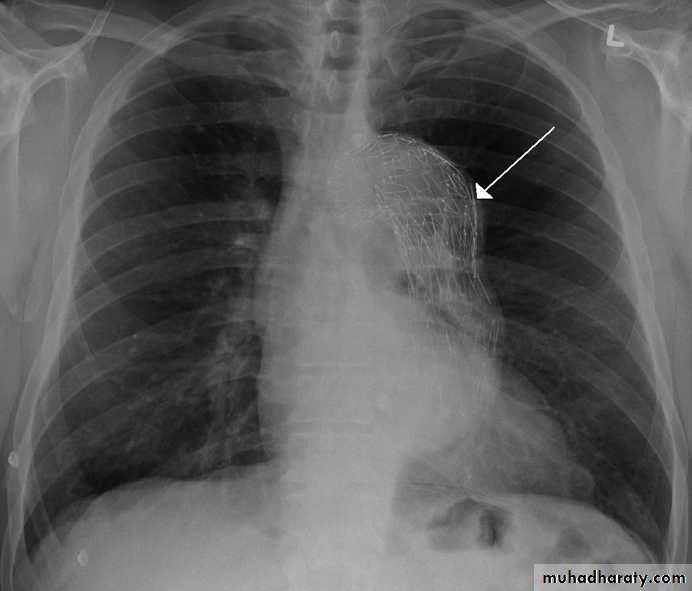

Thymoma.

A chest x-ray (A) reveals an unusual contour over the left hilum (arrows). That the hilum is not obscured (no silhouette sign) indicates that the mass must either be in front of or behind the hilum. A computed tomography scan (B) reveals a soft tissue mass (arrow) just to the left of the aorta. This is the most common location of a thymoma.